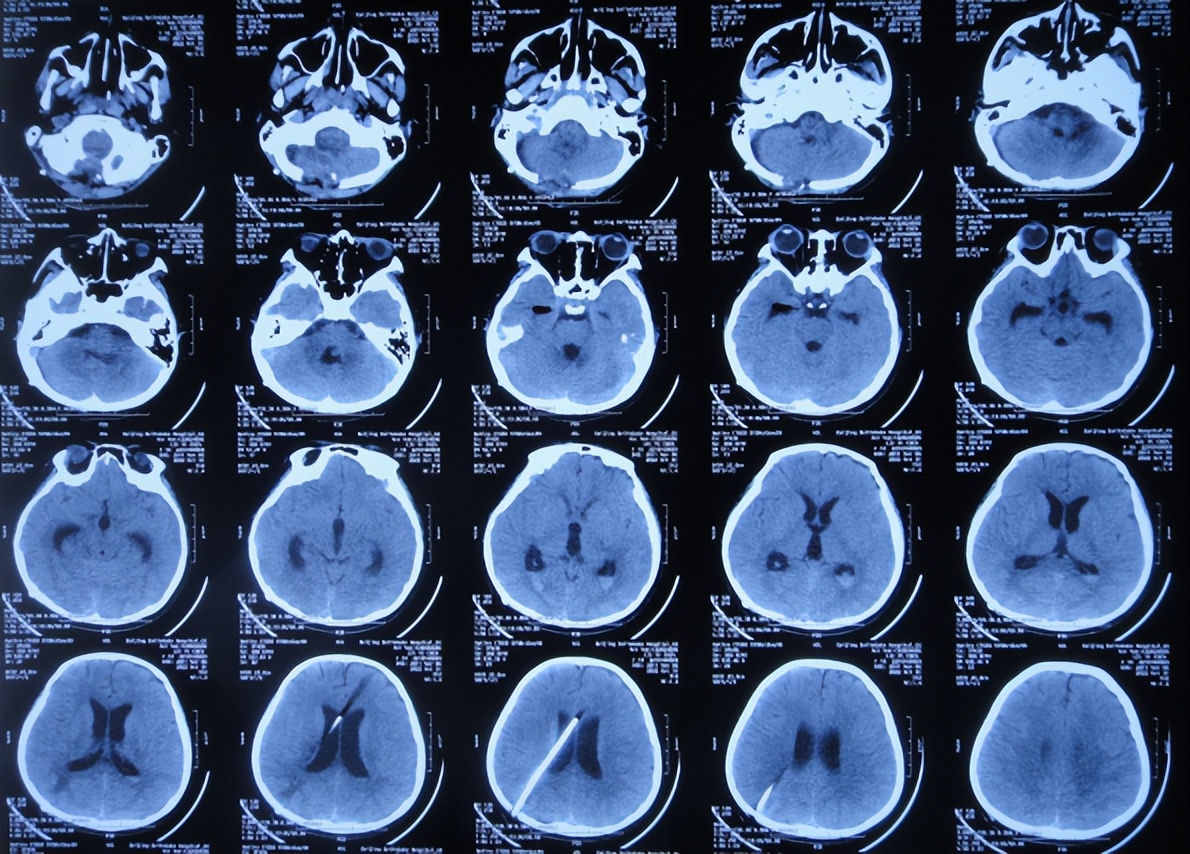

2022年10月16日(小脑出血当天晚上)住入李小勇脑脊液科。入院时:嗜睡,能被叫醒;时有恶心呕吐( 图-2 )。查头颅CT示小脑出血,脑室有扩张( 图-3 );肺部感染( 图-4 )。

图-3: 入院时颅脑CT晚上8点

但脑室腹壁外引流术后2天即2022年10月19日,患儿症状并未明显减轻,查颅脑核磁示脑室有缩小( 图-8 ),计划明日进行脑瘤切除术。

图-8: 2022年10月19日颅脑核磁增强

图-9: 2022年10月20日颅脑CT

2022年10月30日(住院治疗14天),头痛加重,查颅脑CT示脑室又有扩张( 图-12 );肺部感染( 图-13 )。

图-12: 2022年10月30日颅脑CT

2022年12月12日(住院治疗57天),颅脑CT示脑室引流术后状态( 图-15 ),给予夹闭引流管。

图-15: 2022年12月12日颅脑CT

但夹闭5天后即2022年12月17日,患儿出现不适,查颅脑CT示脑室有扩张( 图-16 ),打开引流管。

图-16: 2022年12月17日颅脑CT

2022年12月20日(住院治疗65天),查头颅CT示脑室缩小( 图-17 ),肺部CT示感染好转( 图-18 )。

图-17: 2022年12月20日颅脑CT